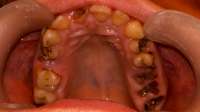

Антуаны, снова нид хелп. Я все тот же Антоний >>512791

Заделал все верхние зубы, в четверг иду ставить брекеты на "верх". Снизу остался 1 зуб с кариесом, его я удалю и вот эта вот хуйня, что я пытался нарисовать на пике выше. Под зубом 46 живет-растет НЕХ. Я оставил КТ терапевту или как там его, он посмотрел и сказал, что видимо когда то залечили мне тот зуб хуевасто, что-то осталось и вот эта хуйня развилась и по-тихоньку хуует там внутри меня. Сказала, что гарантий никаких на лечение дать не может: мб каналы не "пройдет", мб ухудшится ситуация, мб лечение не поможет и придеться удалять - очень шаткая ситуевина. В чем мой вопрос, казалось бы? А вопрос в том: что блядь делать то мне с этой хуйней? Она где то там внутри, жить не мешает, не чувствуется, не видится(ну кроме как на снимке), зуб я тот делал уже и не помню сколько лет назад. МБ 10-12. Но и она и ортодонт говорят одно и тоже: это бомба замедленного действия, может выскочить в любой момент и будет пиздец. Вроде терапевт сказала, что кость там задета этой хуергой или костная ткань. Что-то типа того.

Варианты следующие:

1. Пока есть месяц-полтора до постановки на нижнюю челюсть заняться зубов, просверлить его, положить "лекарство", временную пломбу заделать, надеяться, что пронесет и ставить брекеты. Но есть шансы, что все накроется пиздой, зуб в итоге хуй сохранишь, все мне там распидорасят и будет у меня дыра. А как же тогда брекет лепить? Слепок то делался под все зубы.

2. Нихера не трогать, ставить брекеты, а заняться через полтора года, когда систему сниму. Надеяться, что пронесет. Деньги пустить на сами брекеты, а когда уже все зубы будут как надо, ровные и тд - заниматься этой хренью. Если тогда уж удалять, то думать там - мост/имплант или что.

3. Есть еще мутный третий вариант это ходить по клиникам с этим моим КТ и спрашивать, кто возьмется мне эту херню лечить и будет уверен в результате. Но чувствую, все будут говорить, что гарантий никаких, давай неси бабки и раскрывай рот.

Встанет это все не меньше 10 тысяч, а я так вангую, что 15 точно отвалить придется и хуй бы с ним, если бы результат был, а так можно 15 отдать и в итоге получить дыру.

Грамотный анон, что делать то мне? В четверг пойду к ортодонту, скажу ему, что сказал терапевт, надо будет решение принимать какое-то. В какую сторону мне смотреть?